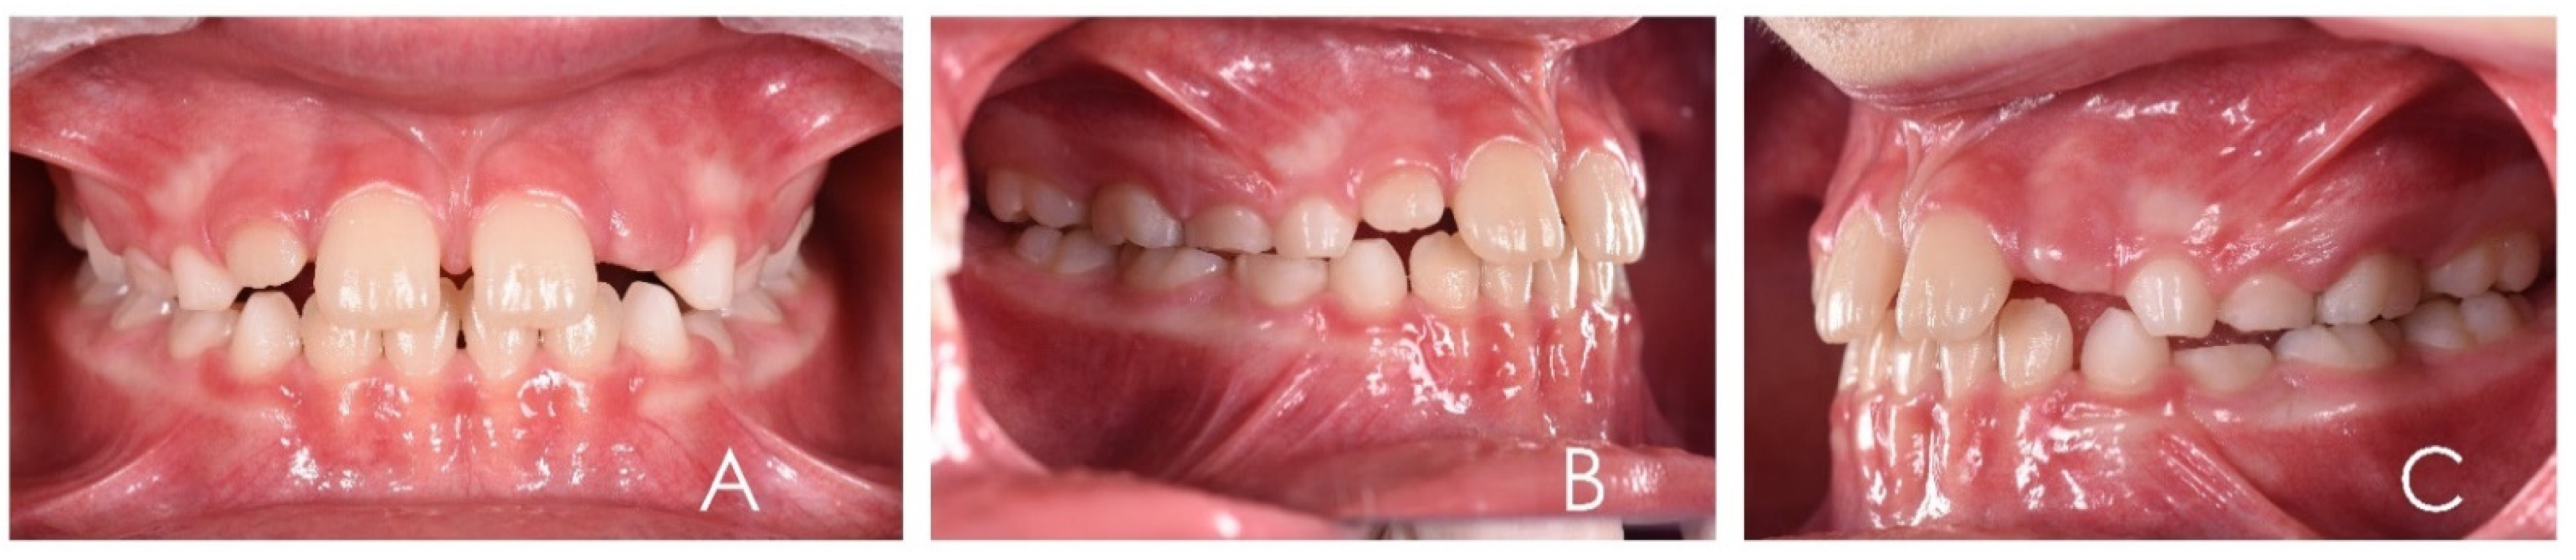

3.1. Clinical Case #1

3.2. Clinical Case #2

3.3. Clinical Case #3

3.4. Clinical Case #4